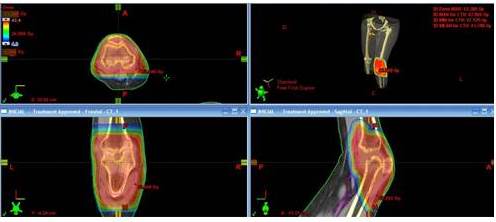

En cuanto a la técnica de RTE empleada, la más utilizada fue la radioterapia con planificación 2D en 51,5 % de los pacientes seguida de técnica conformada con planificación 3D (RTC3D) en 48,5 %. Para la planificación del tratamiento en los casos tratados con RTC3D, se realizó tomografía computarizada con protocolo de radioterapia, con uso de colchón inmovilizador, dichas imágenes obtenidas fueron fusionadas en el sistema de planificación con estudios de resonancia magnética nuclear, esto permitió mejorar la delimitación del volumen a tratar (Figura 1). Posteriormente se realizó el plan de tratamiento, tomando en cuenta la dosis de tolerancia de los tejidos normales y conformando la dosis de la manera más precisa a nivel del volumen blanco (Figura 2). La dosis total promedio fue de 4 400 cGy (rango 1 050 - 5 000 cGy). El tiempo promedio de tratamiento radiante fue de 28 días (rango 8-35).